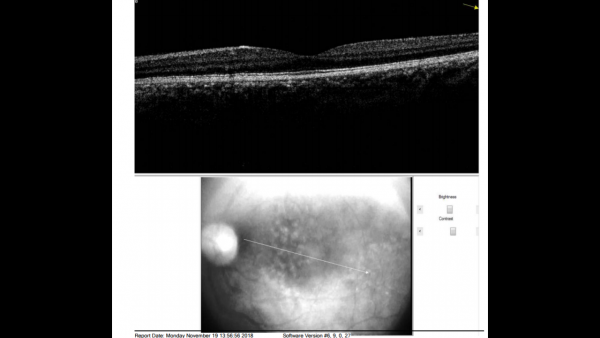

Fundus photos show multiple, yellow, round accumulations sub-RPE. Fundus autofluorescence often demonstrates more numerous hyperautofluorescent drusen than seen ophthalmoscopically. The drusen can demonstrate central hypo-autofluorescence and a rim of hyper-autofluorescence.[6][12] Fluorescein angiography reveals a greater number of small drusen than seen clinically during the early arterio-venous phase. These are spread diffusely throughout the macula, with a classic “stars in the sky” appearance.[6][7] Optical coherence tomography depicts RPE elevations due to drusen beneath the RPE with the most common appearance being a “saw-tooth” appearance as shown in the image below.[6][8]